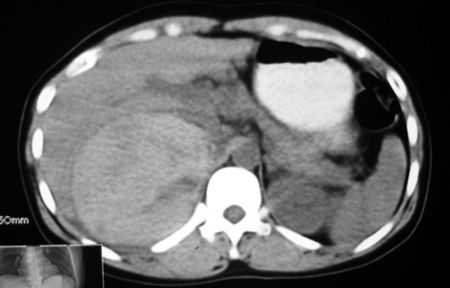

以下是引用bmw011在2009-4-23 13:28:00的发言:[br]考虑右肾包膜下血肿。

以下是引用卜一在2009-4-23 15:43:00的发言:[br]考虑右肾包膜下血肿,不排除占位病变伴出血可能,建议进一步检查。